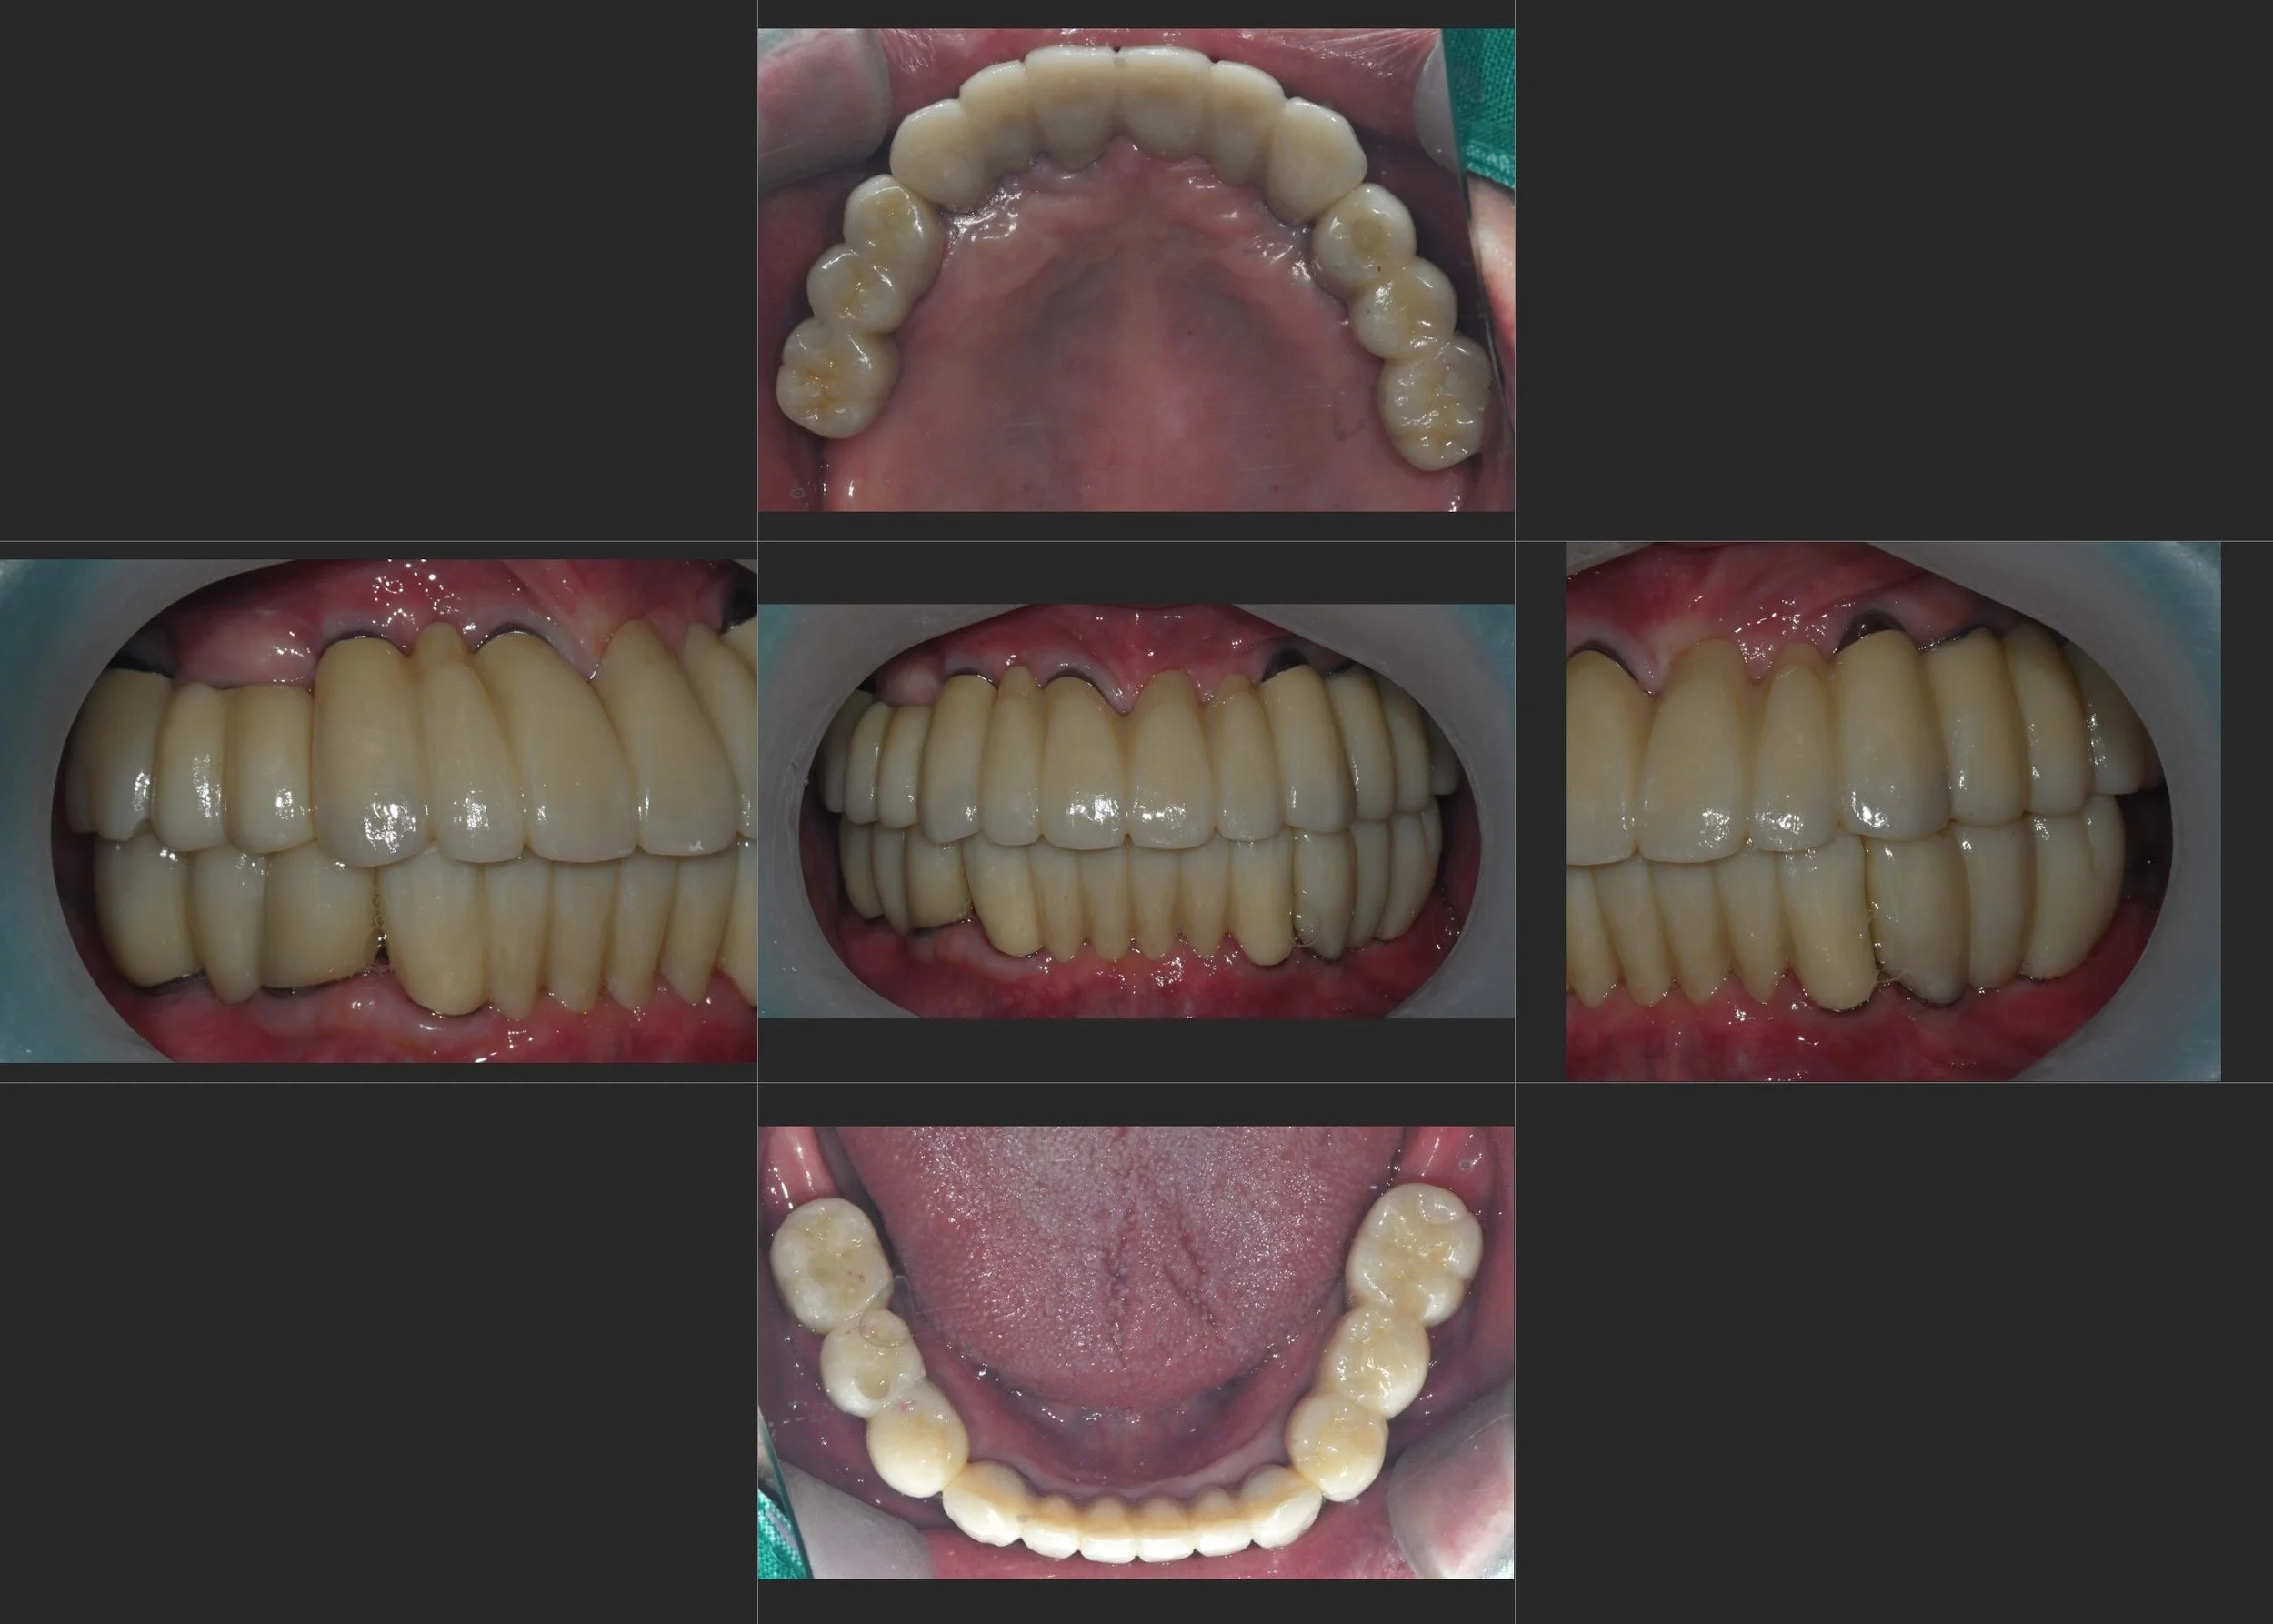

INTRA ORAL - BEFORE

A female patient in her 60s presented with a severely compromised dentition and a completely collapsed occlusal relationship. Long-standing periodontal disease had led to:

• Generalized Periodontal Breakdown: Extensive mobility and loss of supporting structures across both arches.

• Functional Failure: The patient suffered from an inability to chew effectively and expressed dissatisfaction with her facial aesthetics.